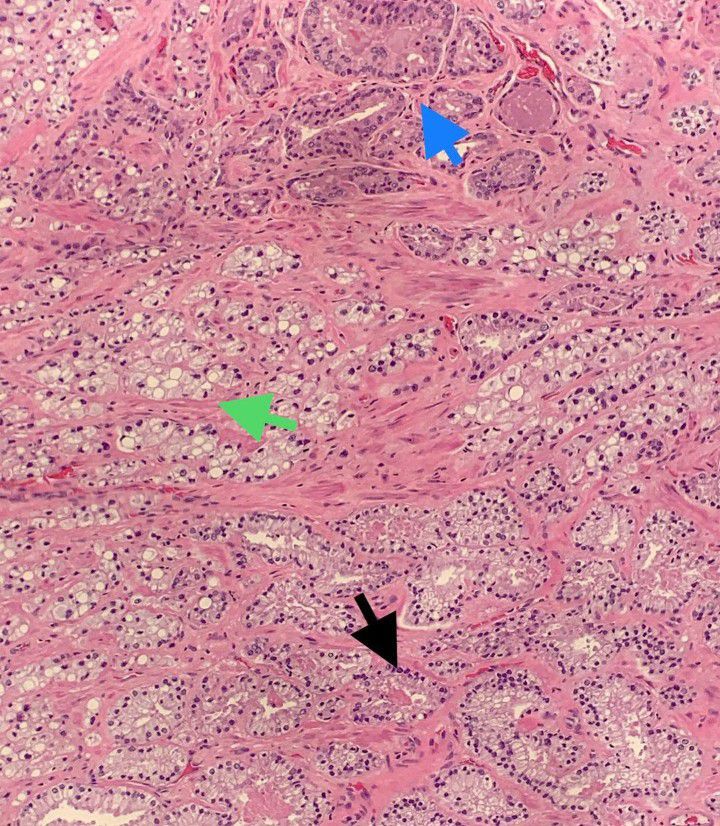

Prostatic Adenocarcinoma

Prostatic adenocarcinoma demonstrating multiple different morphology, which is not at all uncommon.